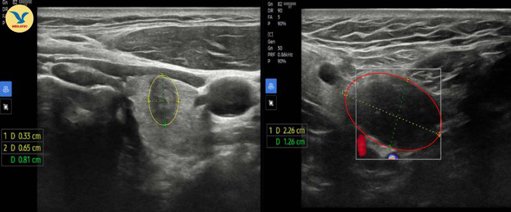

Thăm khám sức khỏe định kỳ tại Phòng khám Đa khoa MEDLATEC Gò Vấp, nam bệnh nhân nhận kết quả ung thư biểu mô tuyến giáp thể nhú thùy trái giai đoạn I, được chỉ định phẫu thuật cắt thùy trái và eo tuyến giáp.